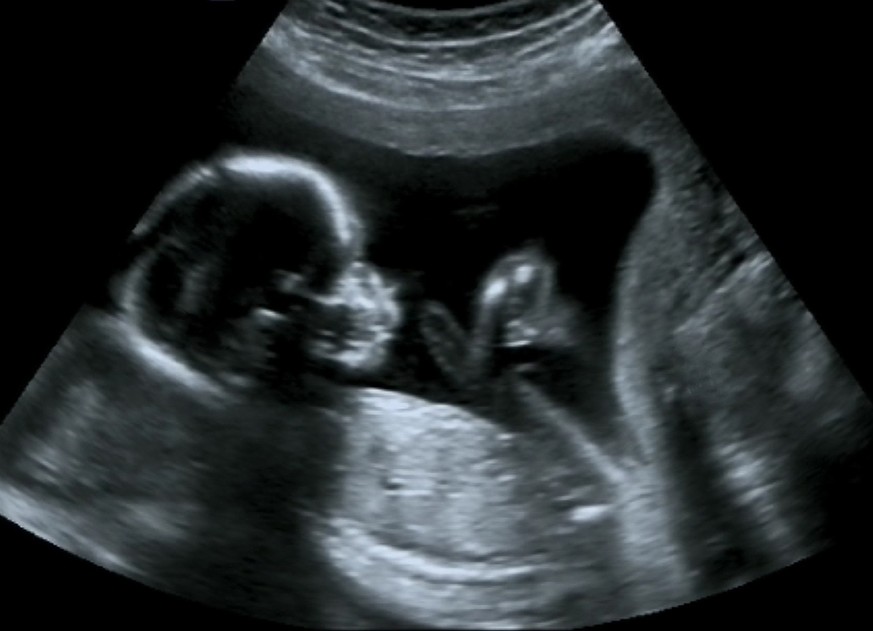

Mädchen oder Bub? Eltern dürfen es erst nach der 12. Woche der Schwangerschaft erfahren

Die Bestimmung des Geschlechts des Embryos oder Fötus bleibt grundsätzlich verboten. Die Information fällt jedoch häufig als Nebenbefund an, etwa bei einer Ultraschalluntersuchung. Um eine Auswahl von Babys nach Geschlecht zu verhindern, will der Bundesrat die Mitteilung des Geschlechts vor Ablauf der 12. Schwangerschaftswoche verbieten.